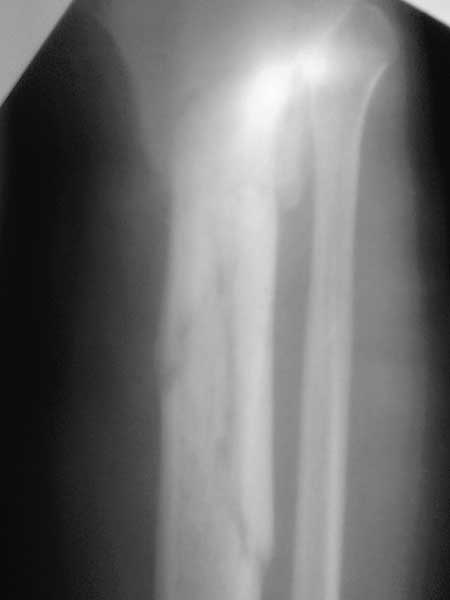

Спасибо за обсуждение.Отправил остальные R, изиняюсь за качество.

3.Перелом на 2 уровнях, есть искривление костно-мозгового канала. Проксимальный отломок короткий.